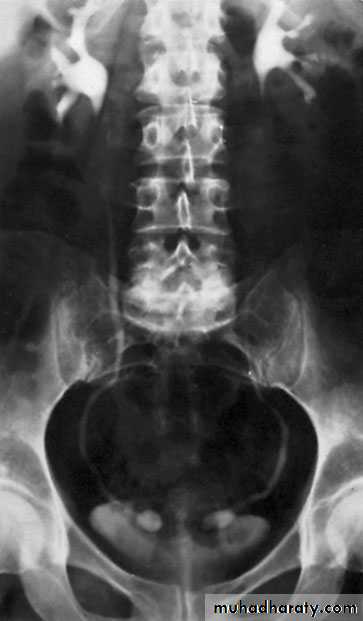

Ureteropelvic Junction (UPJ)(PUJ) Obstruction (stenosis)

The most common cause of significant dilation of the collecting system in the fetal kidneyBoys > Girls

Left-sided lesions predominate

15% bilateral

U/S: hydronephrosisIVU: diagnostic , hydronephrosis with fixed stenotic segment or complete obstruction

CT scan: hydronephrosis that ends abruptly

Bilateral PUJO